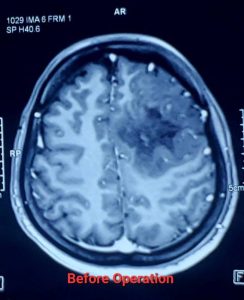

লো-গ্রেড গ্লিওমা (Low-Grade Glioma - LGG)

লো-গ্রেড গ্লিওমা (Low-Grade Glioma – LGG) হলো মস্তিষ্কের টিউমার যা মস্তিষ্কের সহায়ক কোষ (গ্লিয়াল সেল) থেকে তৈরি হয়। এগুলি সাধারণত ধীর গতিতে বৃদ্ধি পায়, তবে সময়ের সাথে সাথে এগুলি আরও আগ্রাসী (উচ্চ-গ্রেডের) হতে পারে। সার্জারি লো-গ্রেড গ্লিওমার চিকিৎসার একটি গুরুত্বপূর্ণ অংশ।

* সর্বাধিক সম্ভব টিউমার অপসারণ (Maximal Safe Resection): নিউরোসার্জনরা যতটা সম্ভব টিউমারের অংশ অপসারণ করার চেষ্টা করেন, যাতে মস্তিষ্কের গুরুত্বপূর্ণ কার্যকারিতার (যেমন – কথা বলা, নড়াচড়া, স্মৃতিশক্তি) ক্ষতি না হয়। কিছু ক্ষেত্রে, সম্পূর্ণ টিউমার অপসারণ সম্ভব না হলেও, আংশিক অপসারণও রোগের অগ্রগতি ধীর করতে এবং লক্ষণগুলি কমাতে সাহায্য করতে পারে।

* নিউরোনেভিগেশন (Neuronavigation) এবং ফাংশনাল এমআরআই (Functional MRI – fMRI): সার্জারির আগে fMRI এবং ডিটিআই (DTI) ম্যাপিং ব্যবহার করে মস্তিষ্কের কোন অংশগুলি গুরুত্বপূর্ণ কার্যকারিতা নিয়ন্ত্রণ করে তা চিহ্নিত করা হয়। নিউরোনেভিগেশন সার্জনের জন্য রিয়েল-টাইম গাইডেন্স প্রদান করে, যা টিউমার অপসারণে নির্ভুলতা বাড়ায়।

* ইন্ট্রাঅপারেটিভ ব্রেইন ম্যাপিং (Intraoperative Brain Mapping): সার্জারির সময় মস্তিষ্কের গুরুত্বপূর্ণ এলাকাগুলি চিহ্নিত করতে এই পদ্ধতি ব্যবহার করা হয়, যাতে টিউমার অপসারণের সময় সেগুলোর ক্ষতি এড়ানো যায়।

লো-গ্রেড গ্লিওমা সার্জারির পর prognosis বেশ ভালো হতে পারে, বিশেষ করে যদি টিউমার সম্পূর্ণ বা বেশিরভাগ অংশ অপসারণ করা যায়। গবেষণায় দেখা গেছে, দ্রুত এবং কার্যকরী সার্জারি জীবনকাল বাড়াতে এবং খিঁচুনি নিয়ন্ত্রণে আনতে সাহায্য করে। যদিও লো-গ্রেড গ্লিওমা সাধারণত ধীর গতিতে বৃদ্ধি পায়, তবুও এটি সময়ের সাথে সাথে উচ্চ-গ্রেডে পরিবর্তিত হতে পারে। তাই নিয়মিত ফলো-আপ এবং প্রয়োজনে অন্যান্য চিকিৎসা,যেমন – রেডিয়েশন থেরাপি বা কেমোথেরাপি, অত্যন্ত গুরুত্বপূর্ণ।